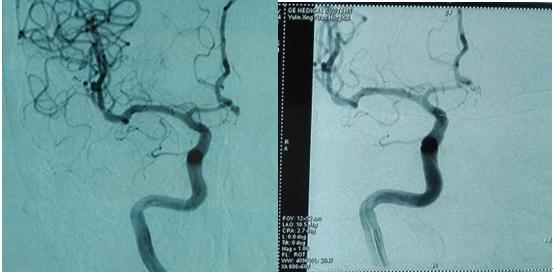

贾振纲副主任医师向记者展示患者手术前后对比图

榆林市一54岁女性患者,以“突发头痛、呕吐2天”为主要原因入院。入院诊断为脑蛛网膜下腔出血、高血压病。发病后在当地医院就诊,效果不佳。入院进行了脑血管造影检查,显示为左侧大脑前动脉动脉瘤,直径2.6-4.0mm。主治医师李建军解释道,这就如同一颗“定时*弹炸**”一旦再出现破裂,后果不堪设想!

在认真分析患者的病情后,尚宏亮主任医师、贾振纲副主任医师、李建军主治医师进行周密准备工作,在全麻下精巧地完成了颅内弹簧圈栓塞术治疗颅内动脉瘤。